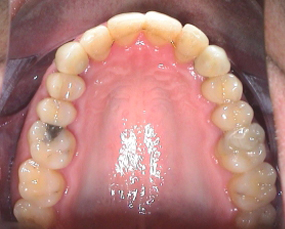

Der Patient hat eine Nichtanlage der oberen seitlichen Schneidezähne. Im Seitenzahnbereich ist die Verzahnung jedoch korrekt. Im Alter von 10-12 Jahren stellten sich die oberen Eckzähne an die Position der seitlichen Schneidezähne. Die Milcheckzähne blieben bis ins Erwachsenenalter im Gebiss. Die Wurzeln der Milchzähne lösen sich im Erwachsenalter auf, sodass sie keinen gesicherten Halt mehr bieten. Als Folge fallen die Zähne aus und hinterlassen eine Zahnlücke. Der hier dargestellte Patient hat einen Milchzahn dann verloren, als er auf einen harten Gegenstand gebissen hat. Es ist dann nur eine Frage der Zeit, bis der andere Milchzahn auch heraus zu fallen droht.

Der verloren gegangene rechte obere Milcheckzahn wurde durch einen Kompositanhänger ersetzt. Der verbliebene (persistierende) linke obere Milcheckzahn wurde sofort extrahiert (gezogen), um dem Alveolarknochen vor der Implantation genügend Zeit zur Stabilisation zu lassen.

Je mehr Platz für die Versorgung mit Implantaten in den Seitenzahnbereich bewegt, desto geringer sind eventuell sichtbare, ästhetische Nachteile. Deshalb entschied man sich in diesem Fall, die oberen bleibenden Eckzähne, in der Position der Schneidezähne zu belassen.

Die odontoplastische Remodellierung gibt den ursprünglichen Eckzähnen eine neue ästhetische und physiologische Form, die einem Schneidezahn entspricht. Dieses zahnärztliche Verfahren erfordert sehr viel Erfahrung und Geschick, ermöglicht es aber, ohne den Einsatz von Teilkronen, Kronen oder Veneers die eigene Zahnsubstanz schonend weitgehend zu belassen. Der Schwede Prof. Björn Zachrisson, hat hierzu schon etliche Veröffentlichungen publiziert. Auf den ersten und zweiten Blick lässt sich nicht mehr erkennen, dass es sich um einen Eckzahn handelt, der hier die Aufgabe und Stellung des Schneidezahnes übernommen hat. Nur die etwas gelbe Zahnfarbe des ursprünglichen Eckzahnes ist noch zu sehen. Durch Bleaching kann dieses Manko auch beseitigt werden und wird erhalten schöne weiße Zähne.

Auf der linken Seite erforderte der frontale Kreuzbiss die Extraktion eines unteren seitlichen Schneidezahnes. Mit Anwendung von T-Attachments und Pointics konnte die Lücke ohne aufzufallen geschlossen werden.